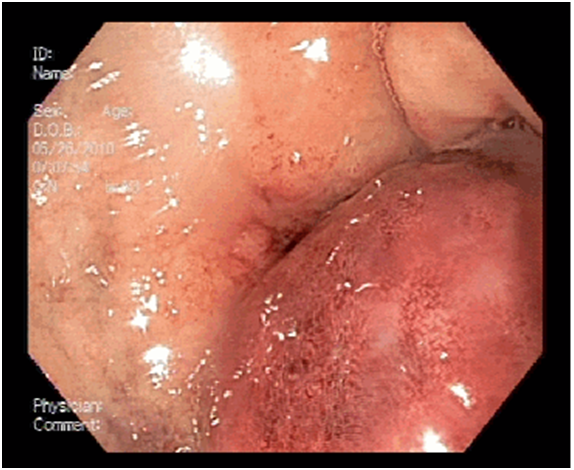

Contrast abdominal tomography was performed, showing pancreas with signs suggestive of chronic pancreatitis and pseudocyst, as well as bulky expansive formation on the wall of the duodenum compatible with hematoma (Figures 1). In digestive endoscopy, the mucosa was located in the posterior wall of the right-pyloric cavity to the edge of the second duodenal portion suggestive of extrinsic compression (Figure 2).

Figure 2 Abutment of the mucosa of these condportion of the duodenum.